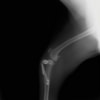

術後左後肢側面像

術前のTPAは左後肢33.1°右後肢26.8°でしたがTPLO実施により左後肢5.5°右後肢12°に矯正されました。